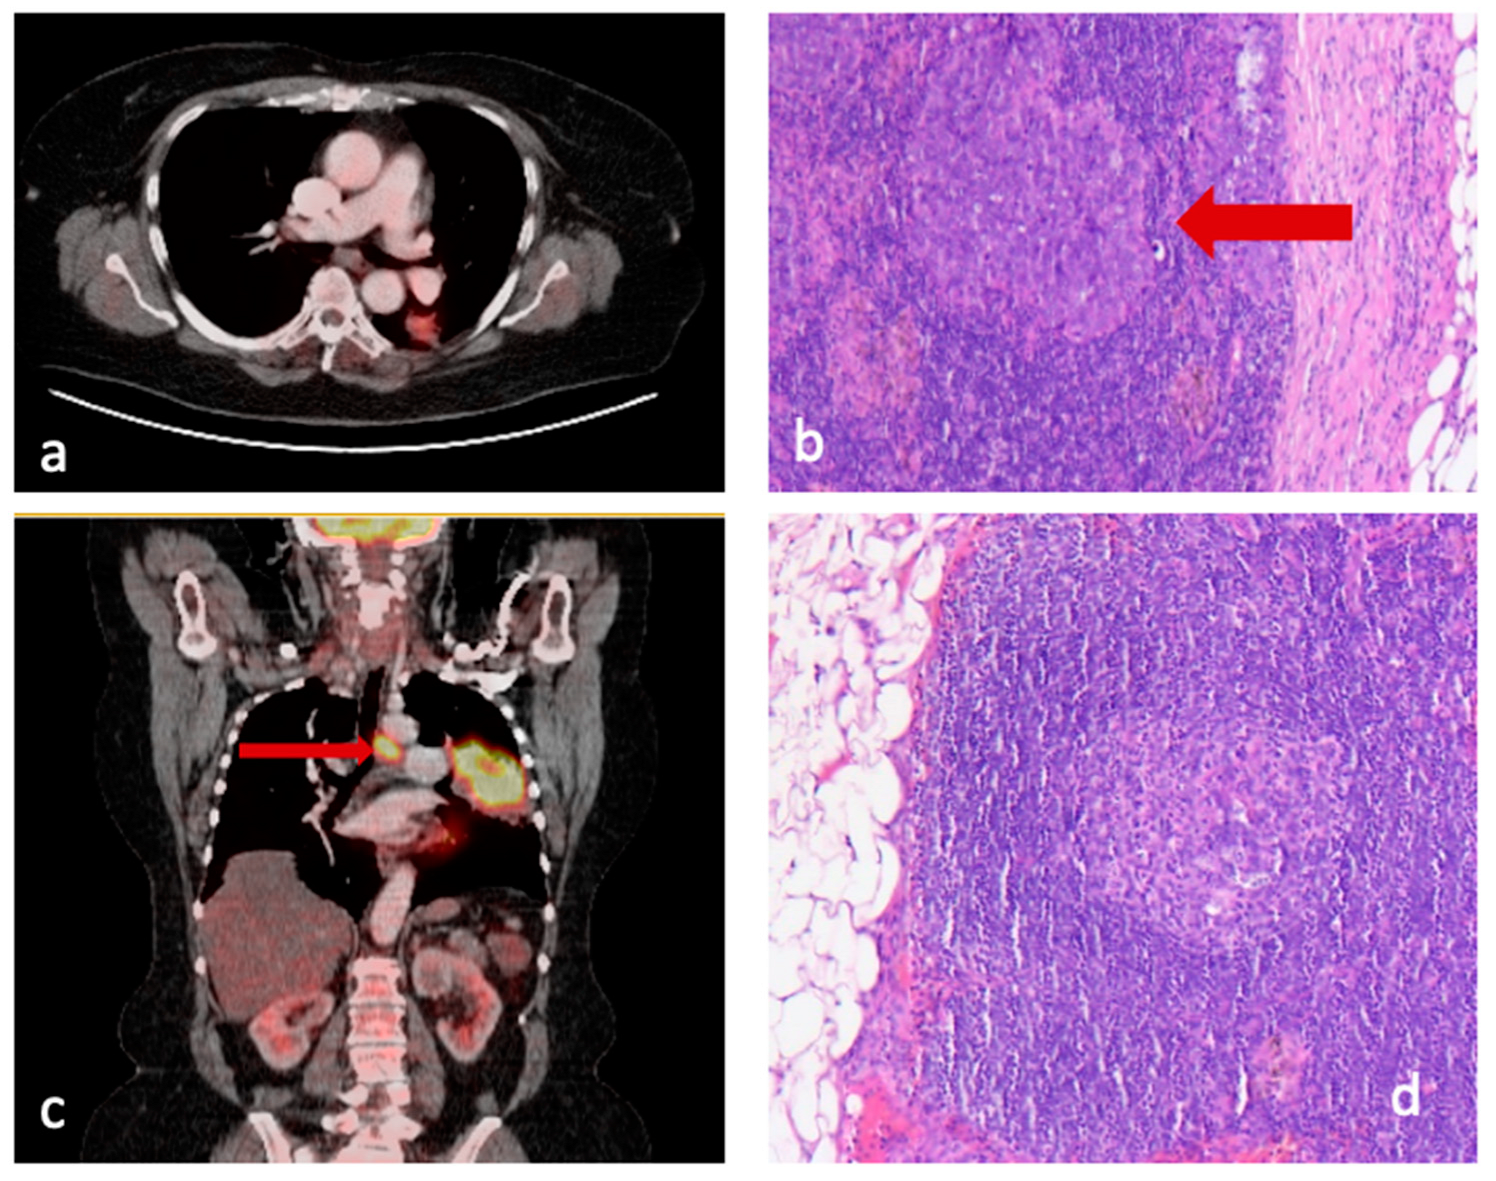

- Group 1 included patients with pathologically confirmed lymph node involvement. Subgroup 1.1 showed no discrepancy between presumed pre- and confirmed postoperative lymph node involvement, whereas subgroup 1.2 patients were PET-negative but had pathologically positive lymph nodes (false negative, Figure 1a,b).

Figure 1. (a) PET/CT scan of patient in group 1.2, where there is no suspected LNM; (b) Pathological specimen of same patient with HE stain showing metastasis; (c) PET/CT scan of patient in group 2.2 with suspected LNM; (d) Pathological specimen of same patient with HE stain showing a lymph node free of disease. - Group 2 consisted of patients with no pathological detection of infiltrated lymph nodes. Subgroup 2.1 showed no discrepancy, but subgroup 2.2. included patients with suspected increased glucose uptake on PET/CT (indicating preoperatively presumed lymph node involvement) but without histopathological confirmation (false positive, Figure 1b,c).